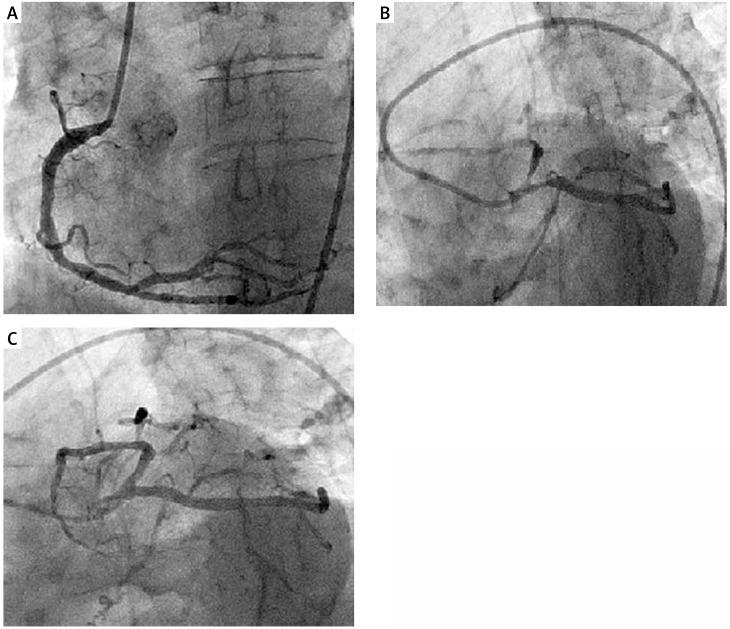

Immunosuppressant agents such as calcineurin inhibitors (CNI) used after solid organ transplantation may cause endothelial dysfunction, and coronary and renal arterial vasospasm. We report a patient presenting acute ST segment elevation myocardial infarction (STEMI) at the second week of renal transplantation. In the case of STEMI in patients with solid organ transplants under immunosuppressive therapy with CNI, coronary vasospasm associated with these drugs should be kept in mind before starting any interventional procedure. High dose nitroglycerine may immediately resolve tacrolimus or cyclosporine A induced coronary vasospasm. Calcium channel blockers should immediately be added to treatment because of the short half-life of nitroglycerine.